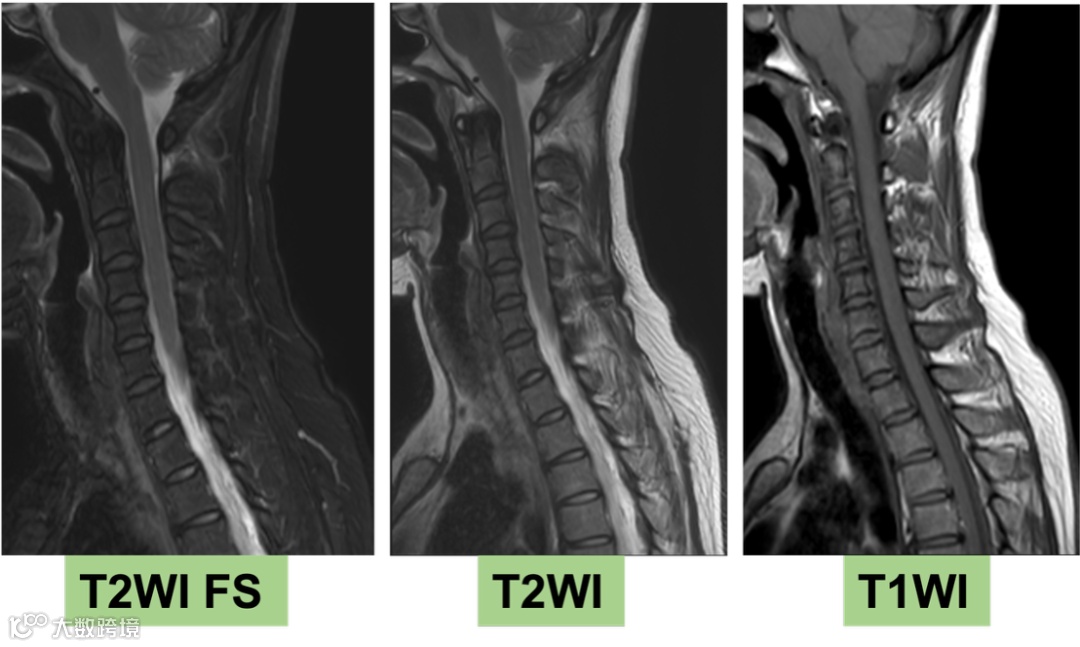

2025-10-14 头颅MR增强+MRV+颈椎MR平扫 影像号:3515491

2025-10-16 颈椎+腰椎MR平扫 影像号:3515491

影像学表现